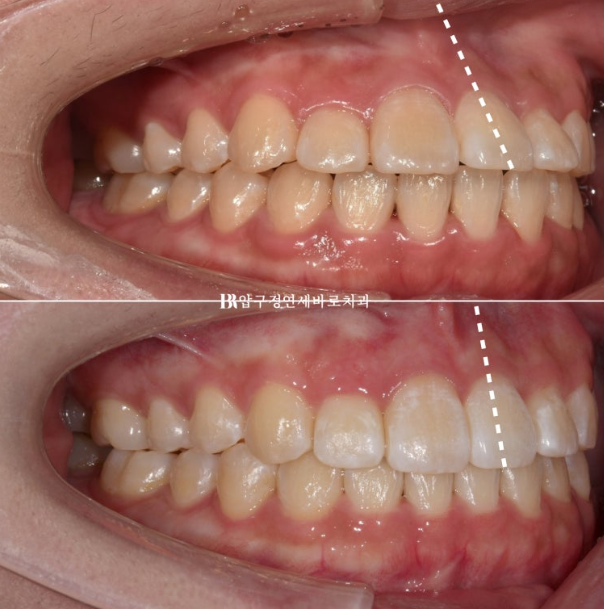

23.04~24.01

앞니 각도 전 후 변화 입니다.